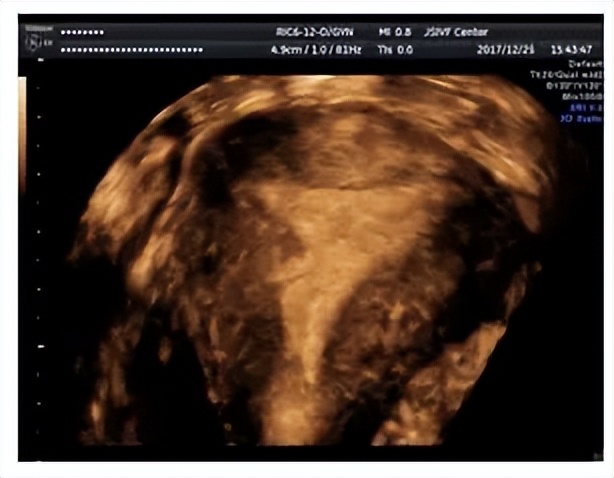

2. 经阴道超声检查(包括三维超声检查)

三维超声检查, 相对于常规阴超可以全方位,多切面,多角度对子宫内膜及宫腔环境进行检查。对诊断中重度宫腔粘连的准确性达90%以上,且方便快捷,对分辨中央性和周围性有诊断价值。建议检查的时候可以选择排卵后月经黄体期时间段进行三维超声检查。